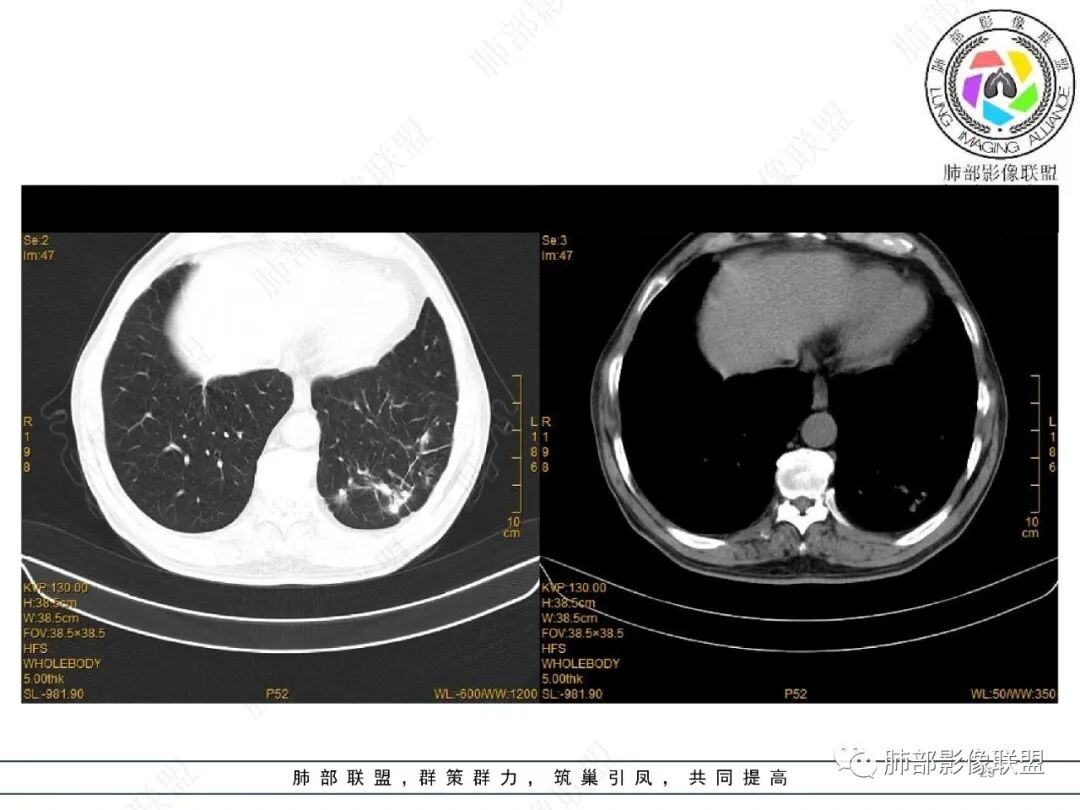

2022.2.17CT显示两肺中内带多发结节影、斑片影、条索影,部分病灶侧向融合与胸膜平行。部分病灶沿着支气管血管束分布、其内支气管稍扩张。部分病灶呈反晕征。大部分病灶边界显示清晰,部分病灶周围可见边界不清的GGO。2022.4.12CT显示两肺中内带多发结节影、条索状、条带状高密度影,边界收缩平直凹陷,大部分病灶沿着支气管血管束分布,亦有位于胸膜下侧向融合与胸膜平行的病灶。总体与第一次CT对比两肺病灶明显吸收。

老年男性,两肺多发病灶,整体呈OP样改变,至于是原发性还是继发性的OP,需要临床鉴别。此病例穿刺结果是隐球菌。该病例CT上缺乏隐球菌典型的“在那遥远的胸膜下,多个蘑菇兄弟,可以侧向融合呈长串状与胸膜平行”影像表现,更多是OP样改变,仅凭临床表现或影像资料诊断隐球菌难度比较大。当然也不除外二元论,导致隐球菌的影像表现被掩盖。

根据宿主的不同免疫状态,影像学差异很大,无免疫抑制的隐球菌病,大概分为4型:孤立结节块型,大片实变型,多发结节或实变型,弥漫型。

注意:多发结节最后经常融合为大片实变